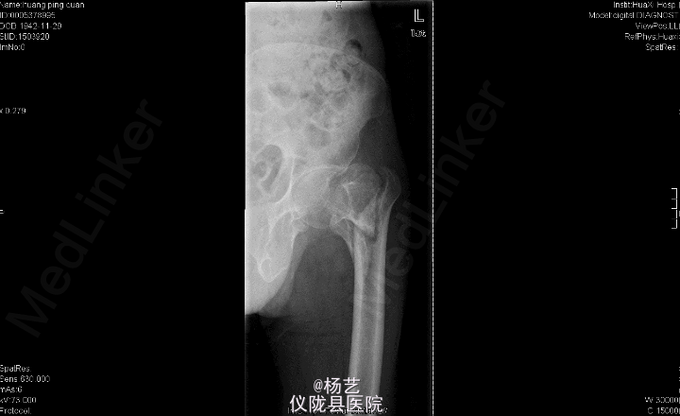

因“摔伤左髋部伴疼痛,畸形,髋关节活动受限8+月”入院。患者于8+月前走路时不慎摔倒,臀部着地,当时感左髋部疼痛,活动加重。无恶心、呕吐、大小便失禁。自行卧床休息及口服中药治疗(具体不详),无好转。隧到当地医院就诊。行X线示:左股骨转子间骨折,给予保守治疗。患者近半年来,左髋部疼痛无明显好转,行走困难。今为行进一步治疗到我院就诊,门诊行X线示:左股骨转子间陈旧性骨折。隧收住我科。 患者98年诊断为:类风湿性关节炎。曾以94年及2008年行腹外疝手术。

专科检查:跛行步态,双手多指指间关节稍屈曲尺偏畸形,左肘关节屈曲畸形。左肘关节及左髋部压痛,左侧肘关节屈曲10°畸形,双腕关节屈10°伸10°左右,活动受限。左髋关节屈伸活动受限,左下肢较右下肢短缩约4.0cm。颈干角85°左右,纵向叩击痛明显Allis征(+)、踝关节活动轻度受限。辅助检查:x线示:左股骨转子间陈旧性骨折。 辅助检查:x线示:左股骨转子间陈旧性骨折。

综上初步诊断:左股骨转子间陈旧性骨折畸形愈合伴髋内翻畸形;类风湿性关节炎累及多关节。 左股骨转子间陈旧性骨折截骨矫形植骨、PFNA内固定术。